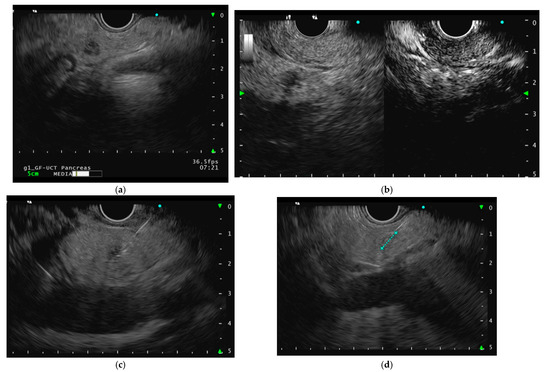

The needle is advanced into the distal portion of the lesion under continuous EUS control. The energy delivery (10–50 Watts) lasts for a few seconds and is automatically interrupted when the temperature or impedance thresholds are reached. Multiple ablations within the lesion may be performed to achieve complete treatment. Precautions are taken to prevent thermal injury to adjacent healthy tissue or the gastrointestinal wall by positioning the needle at the lesion’s distal margin and delaying device withdrawal after energy application. The use of contrast-enhanced harmonic with the injection of an ultrasound contrast agent is recommended to assess the residual vital tissue after ablation [26,27]. Schematic representations of an EUS-RFA procedure for a 7 mm F-pNEN of the pancreatic neck is reported in Figure 1.

Figure 1.

(a) Endoscopic ultrasound image of a small hypoechoic insulinoma (functioning pancreatic neuroendocrine neoplasm) of the pancreatic neck; (b) contrast-enhanced harmonic endoscopic ultrasound (CH-EUS) after the injection of an ultrasound contrast agent showing a homogeneously hyper-enhanced neoplasm during the arterial phase, with a peripheral rim; (c) the 7 mm endoscopic ultrasound radiofrequency ablation probe (EUSRA, Taewoong Medical) insertion; (d) accurate tip control under endoscopic ultrasound evaluation; (e) EUS-RFA application at 40 Watt power setting, confirmed by the appearance of hyperechoic bubbles suggesting coagulative necrosis; (f) contrast-enhanced harmonic endoscopic ultrasound (CH-EUS) after the injection of an ultrasound contrast agent showing complete ablation with no residual vital tissue.